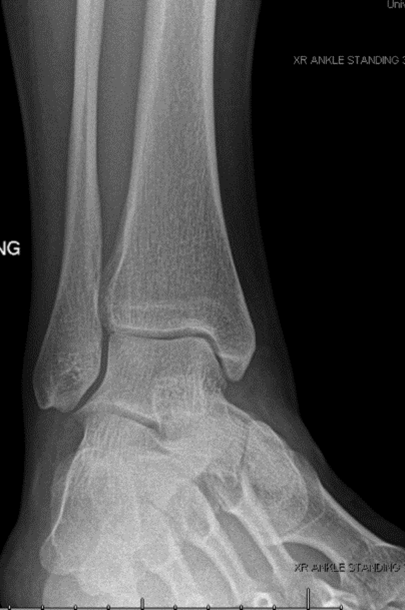

Figure 1-Normal ankle jointNormal Ankle Joint Anatomy

Three bones join to form the ankle joint. They include the shin bone or the tibia, the thinner bone going along the tibia known as the fibula, and the foot bone located above the heel bone known as the talus.

The bony protrusions seen and felt over the ankle joint are the malleoli. These include the medial malleolus which forms the base of the tibia and is felt on the inside of the ankle, the posterior malleolus which also forms the base of the tibia and is felt on the back of the ankle, and the lateral malleolus which is the low end of the fibula and is felt on the outside of the ankle.

The ankle joint allows up-and-down motion of the foot and the subtalar joint, located below the ankle joint, allows side-to-side motion of the foot. Bands of tough fibrous tissue known as ligaments surround the ankle joint and subtalar joints attaching the bones of the leg to each other and to the bones of the foot.